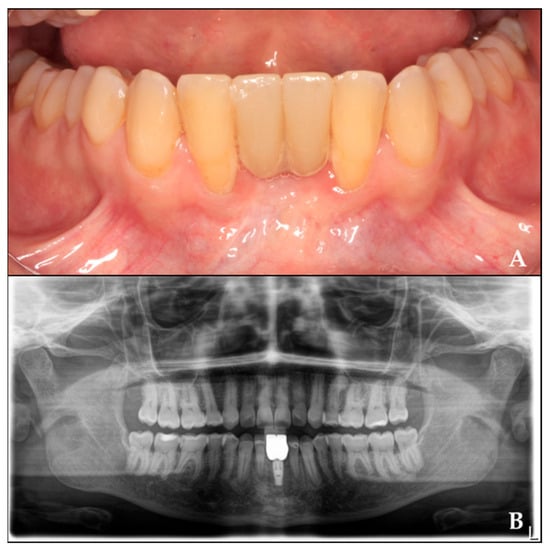

4. Fixed Prosthesis Placement

Four months after implant placement, the prosthetic restoration was placed. After a two-year follow-up, the radiograph shows the final outcome (Figure 8).

Figure 8. Rehabilitation of the regenerated area with crowns twenty months after implant placement. (A) Prosthetic rehabilitation in the regenerated area. (B) Orthopantomography with crowns over the implant.

This clinical case demonstrates a successful approach to guided bone regeneration, achieving 8.8 mm of bone height gain and 7.6 mm of width, as well as the formation of keratinized gingiva.

While established methods such as Urban’s approach (using either resorbable membranes or PTFE) [25] and the Khoury technique [19] have demonstrated reliable bone gain outcomes, titanium occlusive barriers offer distinct clinical advantages. Our results show this approach provides similarly effective vertical (8.8 mm) and horizontal (7.6 mm) bone regeneration [13], while being significantly less invasive. The decision to employ any particular regenerative technique should be made after careful consideration of three factors: the specific bone defect characteristics, individual patient anatomy and biology, and the surgeon’s technical expertise with the procedure.